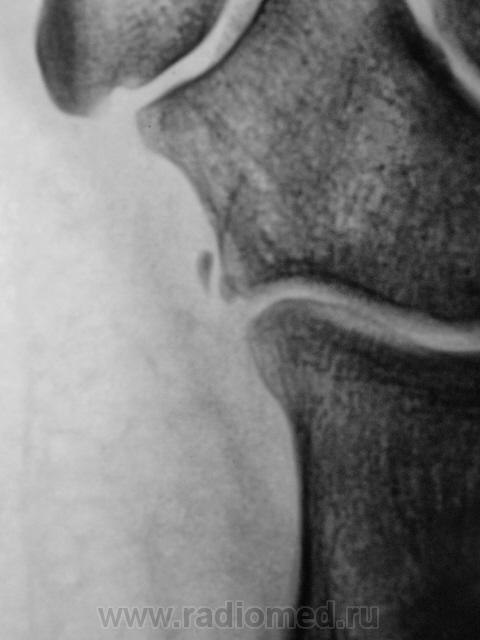

Травма.   Пациент направлен на рентгенографию стопы.

не увеличение, то такой перелом очень легко пропустить.

Os peroneum, сверхкомплектная кубовидная

кость, может являться сесамовидной костью в

сухожилии длинной малоберцовой мышцы.

Os calcaneocuboideum laterale, добавочная

кость, возможно, что это образование

является персистирующим апофизом латерально-

верхнего края пяточной кости или прилежащим

краем кубовидной кости.

Мелкие кости, действательно, не похожи на отломанные фрагменты. Но в кубовидной кости имеется линия, подозрительная на перелом, а кость эта, хоть и редко, но ломается.